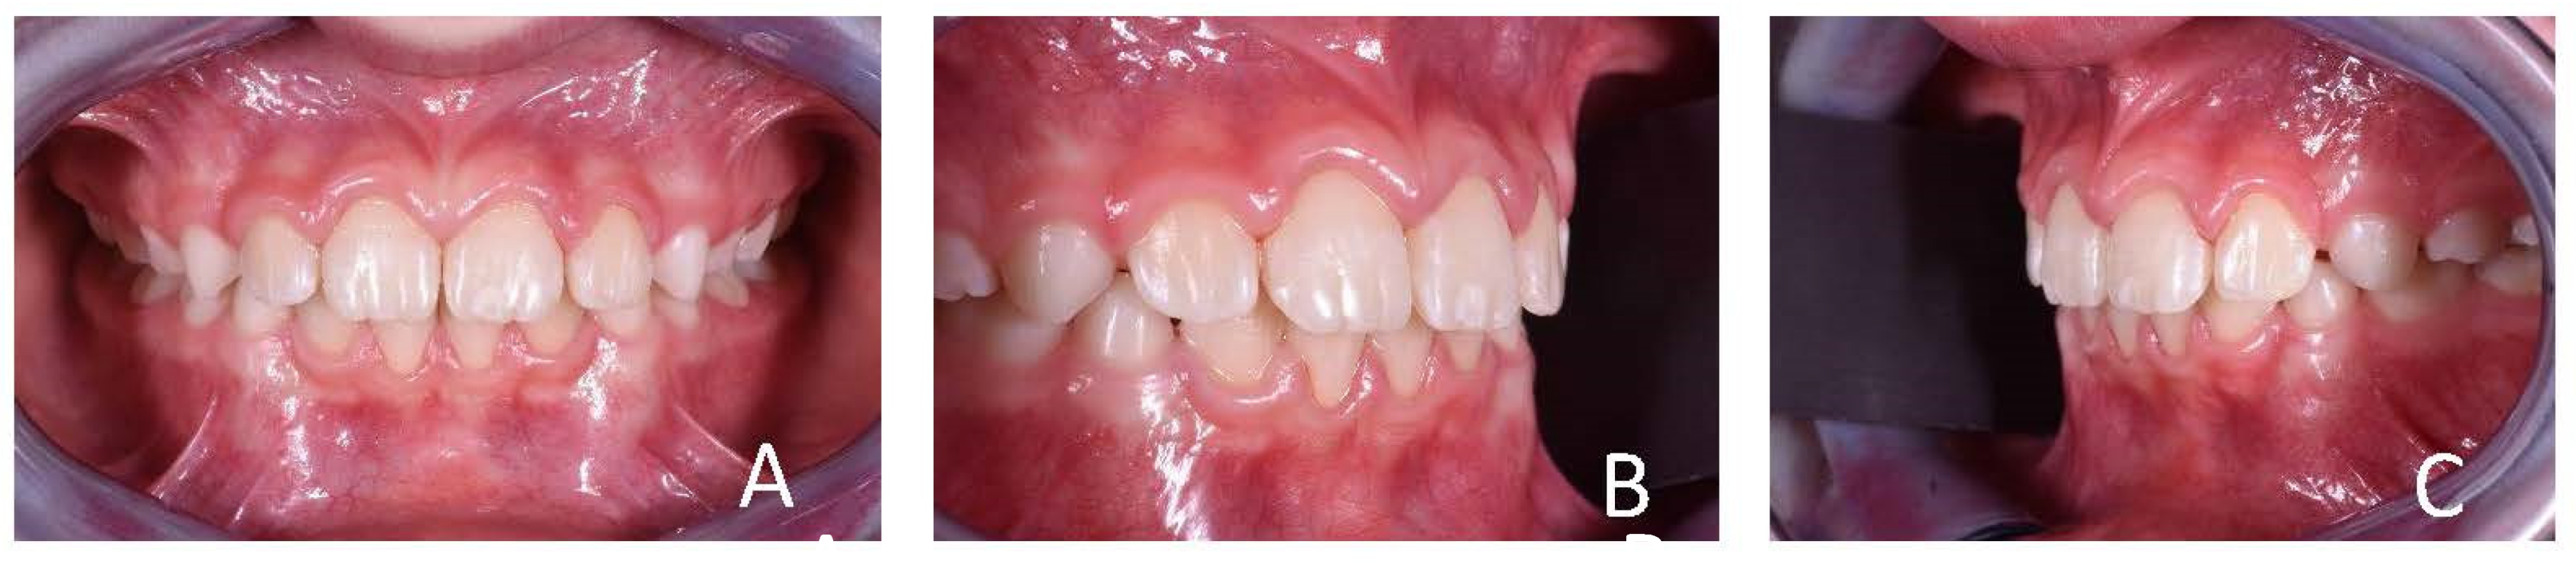

3.1. Clinical Case #1